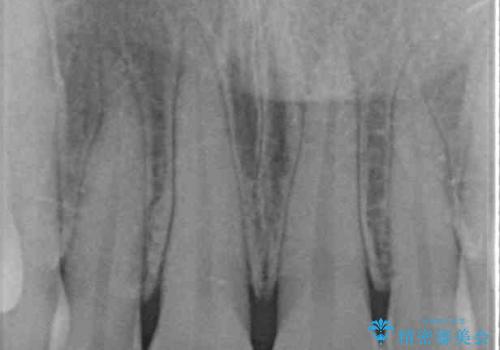

- 転んだ際に欠けてしまった前歯の変色が気になるとのことで来院された患者様です。

診察やレントゲン写真より神経組織の失活が認められたため、根管治療、ファイバーコアによる土台築製後、オールセラミッククラウンにて補綴することとしました。